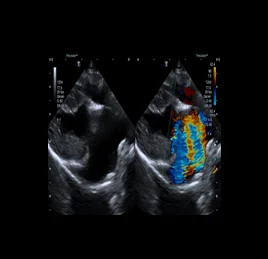

초음파 검사는 고주파 음파를 이용해 장기와 조직의 실시간 움직임을 영상으로 확인하는 비침습적 진단법입니다.

장기의 구조뿐 아니라 혈류, 운동성, 기능 변화까지 평가할 수 있어, 다양한 질환의 조기 발견과 모니터링에 효과적입니다.

• 퇴행성 판막질환

• 동맥관 개존증 - PDA

• 폐동맥고혈압